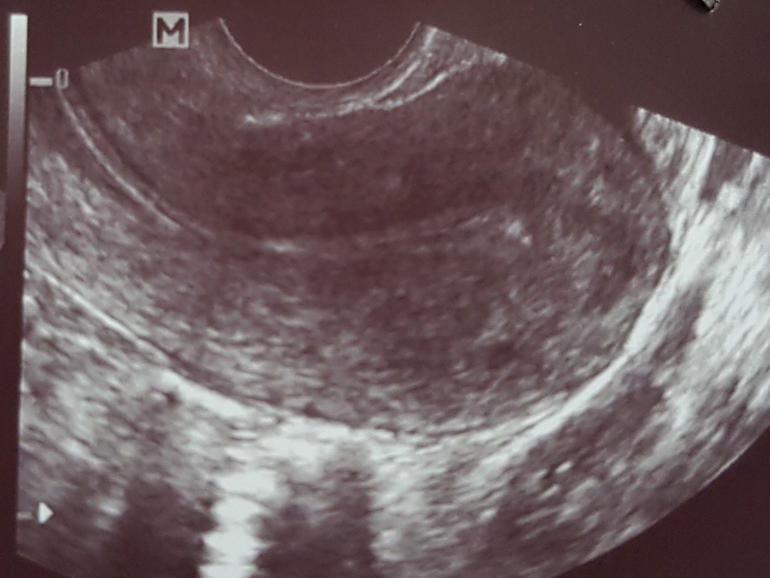

В этом цикле что то странно, прыщи на лице, грудь немного чувствительна прям сразу еще до о. Сегодня 10дц, пошла я на узи посмотреть что там. В яичниках по 7-8 фоликов, в одном 3-5мм и в другом 7-8мм. Доминантного я так поняла еще нет. Эндометрий узистка сказала маленький 6мм и не соответствует 1й фазу цикла, имеет какие то включения. Намекнула что в этом цикле не получится.